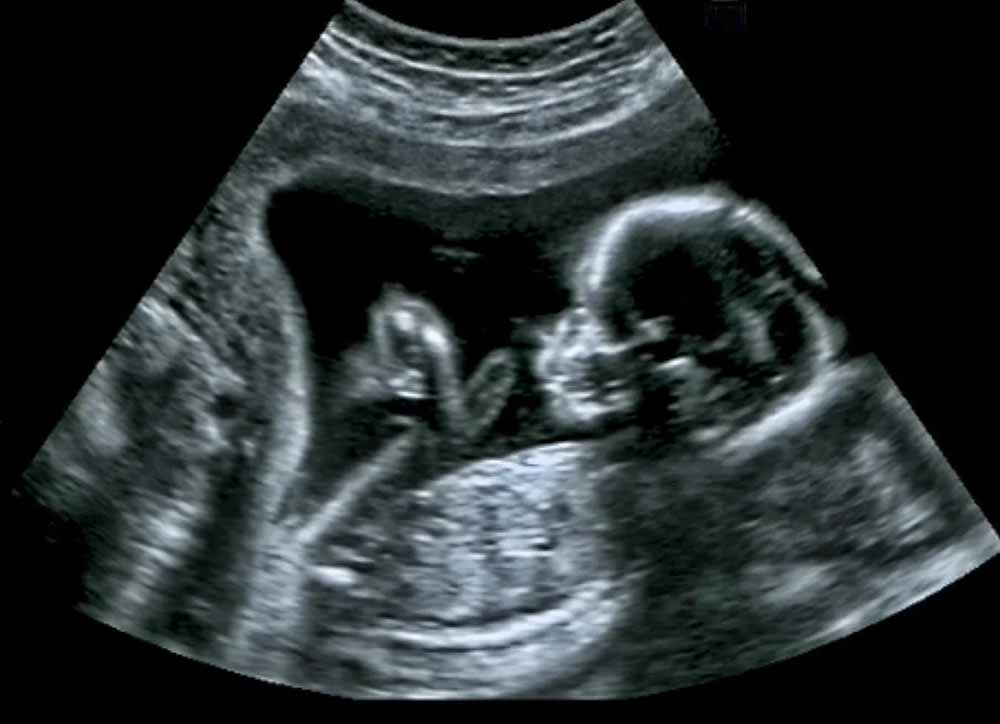

Even a fetus can yawn: Researchers have found that a human fetus can yawn during the first trimester in the womb. The reason is still unknown. A 2012 analysis of 4D scans was able to differentiate between a growing baby opening its mouth and a ‘non-yawn mouth opening,’ despite the fact that academics had previously contested imaging of open-mouth fetuses.